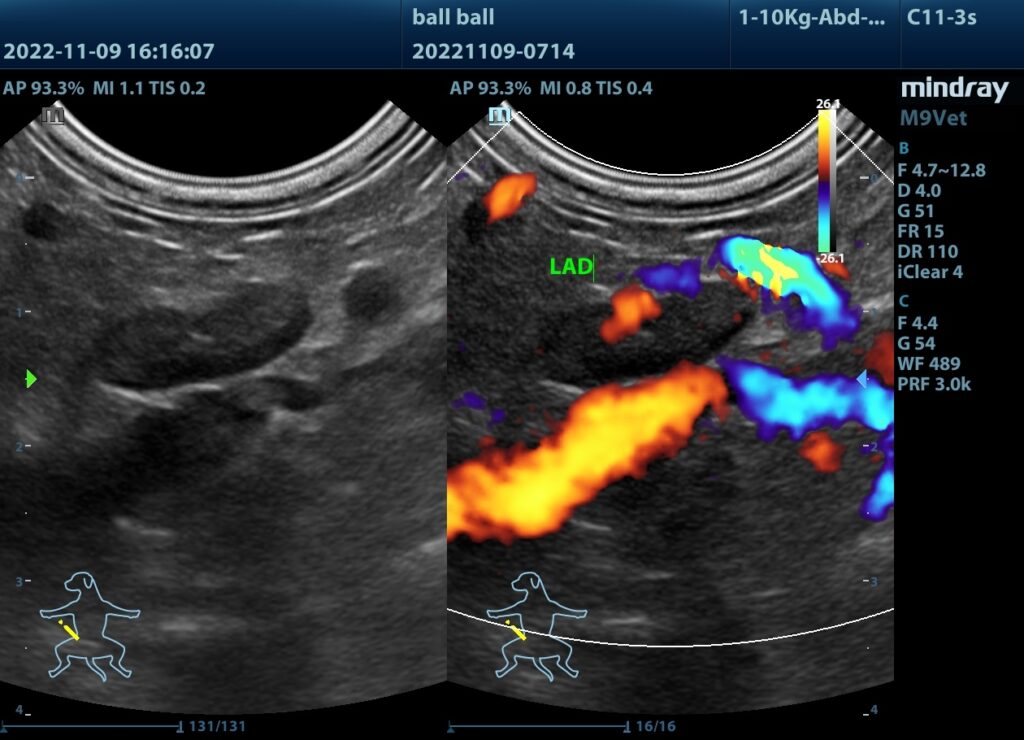

(2)超音波看見腫大的腎上腺。

腫大的腎上腺